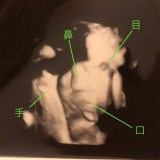

入院生活21日目amebajp/img/user/pe/petittulip/1753780gif">32w6d 入院生活も3週間たって すっかり病室が 自分の住みかとなって来た 入院当初は旦那に アレ持って来て!家のアソコあるからー と言えたけど… 今は家のどこに置いたか 記憶が薄れて来た 今日は腹部エコーで 赤ちゃんを診てもらいました 相変わらずあまり見えなかったけど なんとなーく顔かなーくらい 体重は1730g また少し大きくなってたー 順調みたいです エコーしてもらってる時 先生と退院のはずだったのにね〜 なんて話してて 先生が 『34週になったら2時間くらいは 外出出来るようにするからー』 『ストレス溜まるからねー』 と… 私『はい!ありがとうございます』 なんて言ったけど… と言うことは… 私は34週まで ココにいるってことでしょうか と あとから心の中でつぶやきました ていうか… 34週で外出と言うことは その後も入院してるってことだよね と言うことは 36週まで入院ですか と言うことは 退院はあと1ヶ月も先ですか 先生が元気よく言ってくれるから 先生の調子に乗っかって 元気よく答えちゃったけど あとから一人で アレレとなりました どーも私は その場で人に質問返しが出来ない 相手の話し方のペースに 持ってかれるみたいな… (頭の回転が遅いからかな…( ;∀;)) いつもあとから 1人心の中でアレレとなります 次の診察の時に聞いてみよー 朝ごはん 昼ごはん ビーフストロガノフ美味しかったー おやつ イチゴの三方六 北海道では有名なお菓子 ホント入院してると 色んなお菓子食べれるー そして友達が またたくさん持って来てくれたー 毎日一つずつ大切に食べよー 今日は2つ食べちゃったけど 夜ご飯※主食は全て半量です メイクの上から塗り直せる!プライバシーのUV! 続きを見る ['close']